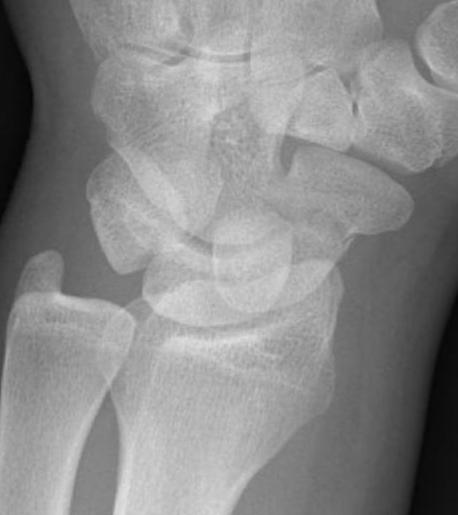

CT

Indication: any potential displacement

Position: patient prone with fully pronated hand over head

Instability

- displacement > 1mm on any film

- intra-scaphoid angle > 35o

- comminution

- proximal pole fractures

- perilunate trans-scaphoid dislocation

Scaphoid waist fracture 1 mm displaced

Scaphoid fracture with significant displacement

Scaphoid proximal pole fracture